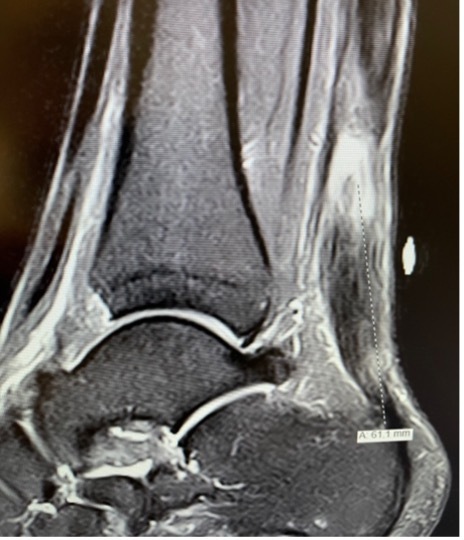

A 31-year-old male presented with a chronic tear in the midsubstance of his right Achilles tendon. The patient had no active motion and walked with a “slapping foot gait.” His pre-operative dorsiflexion was 4-/5+ and he had no strength in plantar flexion. MRI of the tendon showed cavitation and infiltration of dense fibrous tissue indicative of the chronic nature of this rupture with the likelihood of poor-quality tissue (Figure 1). The middle of the tendon consisted of degenerative, retracted tissue. Scarring was likely due to the fact that 8 weeks had elapsed since the time of injury.